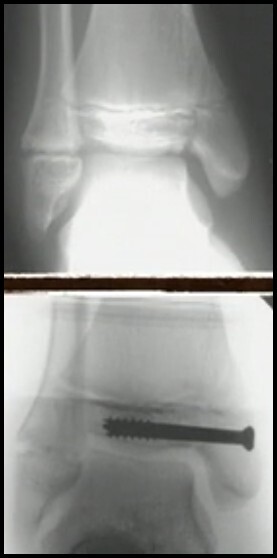

TRIPLANAR

* Força de Rotação Externa

* Paciente mais jovens em relação Tillaux (mais fise aberta)

* SH4 (Parece SH3 no AP e parece SH2 no Perfil)